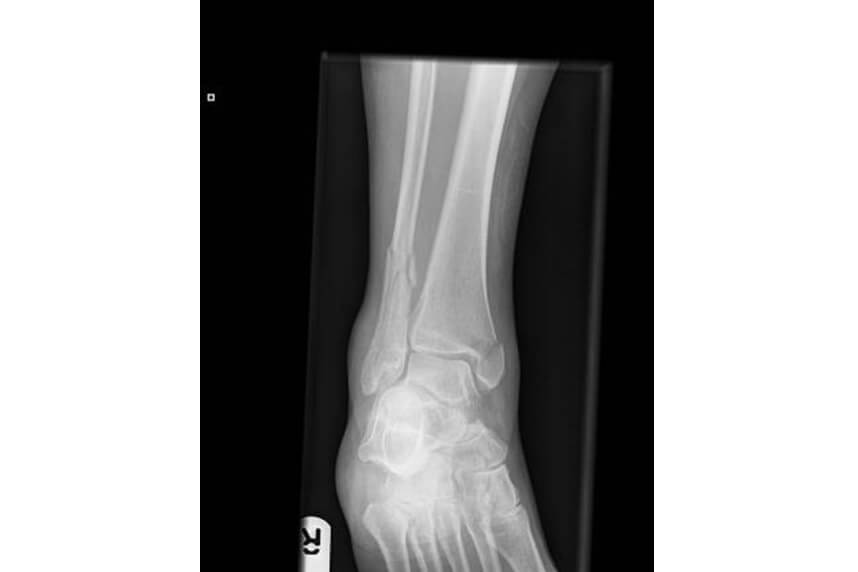

Fracturile de stres sunt foarte frecvente la sportivii de

performanta. Acestea au loc datorita incarcarii repetate a

osului.

Diagnosticul se pune in urma unui examen clinic foarte precis in

care se tine cont de modificarile stilului de antrenament sau

incarcare in timpul antrenamentului. Exista mai multi factori

predispozanti care pot creste posibilitatea aparitiei unei

fracturi de stres, printre acestia se enumera si exersarea pe

suprafete dure, variatia calitativa si cantitativa a incarcarii

in functie de sex si varsta.

Cei mai afectati de acest tip de fracturi sunt alergatorii de

distante lungi, soldatii si varstnicii. La aproximativ 2-3

saptamani dupa producerea fracturii initiale, durerea devine

insuportabila iar pacientii nu gasesc alta solutie decat sa

intrerupa in totalitate, sau aproape in totalitate activitatea

fizica. Diagnosticarea trebuie facuta cu multa grija deoarece pot

fi cazuri unde timp de 14-15 zile fractura nu este vizibila la

radiografii. Din acest motiv se recomanda efectuarea unui CT sau

RMN pentru a confirma diagnosticul si a evalua gravitatea

acestuia.

Tratamentul difera in functie de localizare si intensitatea

fracturii si poate varia de la o perioada scurta de imobilizare

concomitenta cu inceperea kinetoterapiei, la o imobilizare de

lunga durata in aparat gipsat si in unele cazuri chiar o fixare

chirurgicala.